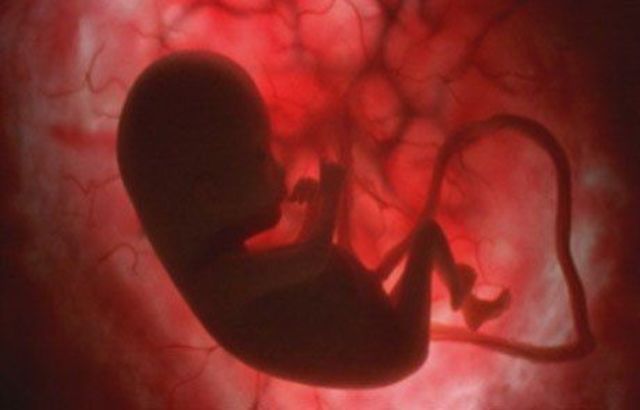

El embrión a formado todos los órganos. Las extremidades ya están formadas. El embrión se mueve y disfruta de todo su espacio dentro del saco amniótico.

Mide 5,5 cm y pesa 9 g. Poco a poco, su cabeza está más erguida y va tomando forma redondeada.

Los ojos, cubiertos por unos finísimos párpados, se van situando en la parte delantera de la cara y sus orejas avanzan hacia su ubicación definitiva.

Las fosas nasales están todavía bastante separadas.

Las cuerdas vocales hacen su aparición.